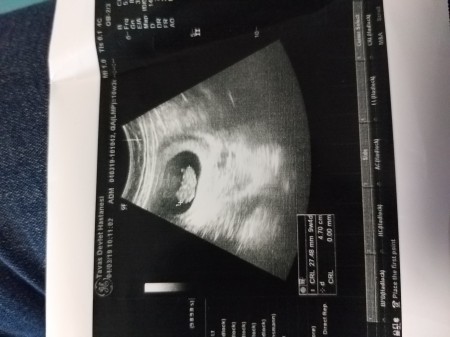

kizlar cinsiyet tahmini lutfen

Gebelik haftası 9+4

O daha çok minik annesi cinsiyeti öğrenmek için çok erken. Değil biz doktora gitsen o bile daha cinsiyetini tahmin edemez canım: )

Bencede kız ama 11 12 haftalıkken nub açısında daha kolay tahmin ediliyor ben çoğu arkadaşımı tahmin ettim en azından

Arkası dönük galiba içimden kız geçti canım ya saglıklı olsun inşallah